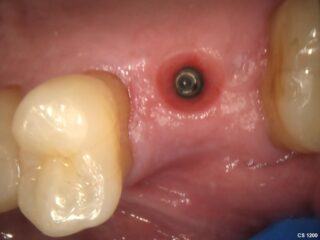

During the healing phase, a small healing cap is used to protect the implant and shape the surrounding gum tissue, preparing the area for the final crown or bridge.

After a problematic tooth is removed, the jawbone is left to heal and prepare for a dental implant. This step is essential for the long-term success of the treatment.

A dental implant, usually made of titanium, is placed into the jawbone. Over time, the implant fuses with the bone to create a solid and stable foundation.